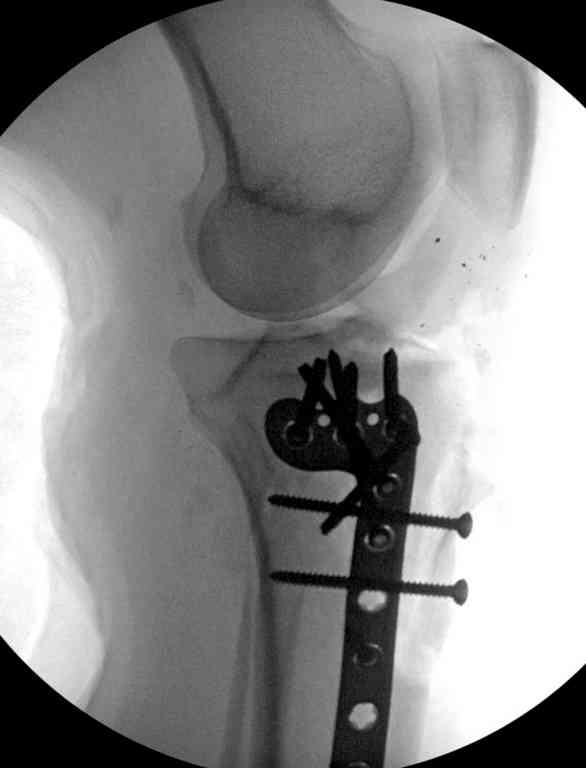

Имя     : 24 gsw plate.jpg

Тип     : image/jpeg

Размер  : 33269 байтов

Описание: отсутствует

Url     : http://weborto.net:8080/pipermail/ortho/attachments/20100916/b1b36bf2/attachment-0010.jpg